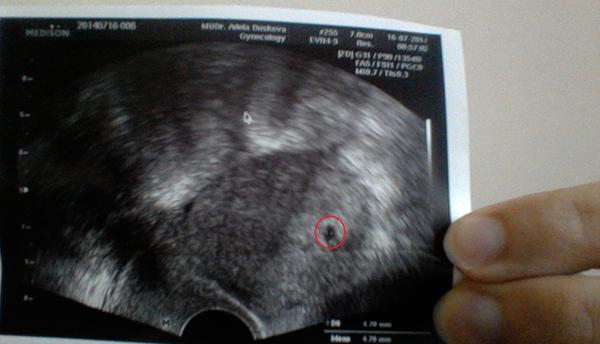

@maia74 , @pampalin @zelvicka373 omlouvám se že vstupuju s trochu jiným dotazem ale jsem na tom podobně jako zakladatelka. jen mám doktorku která mi nic moc nevysvětlila a já se snažím vyluštit údaje z fotky ultrazvuku. Prosím vyznáte se v tom někdo a která ta číslíčka a písmenka znamenají velikost?

@cukrik123 Na fotce z UZ je napsáno CRL a to je velikost a vedle by mělo být napsáno třeba 8w2d a to je stáří 8+2

@maqggienka hele jsem asi slepá ale nevidím to tam mám uz ve fotkách prosím navedeš mě ?